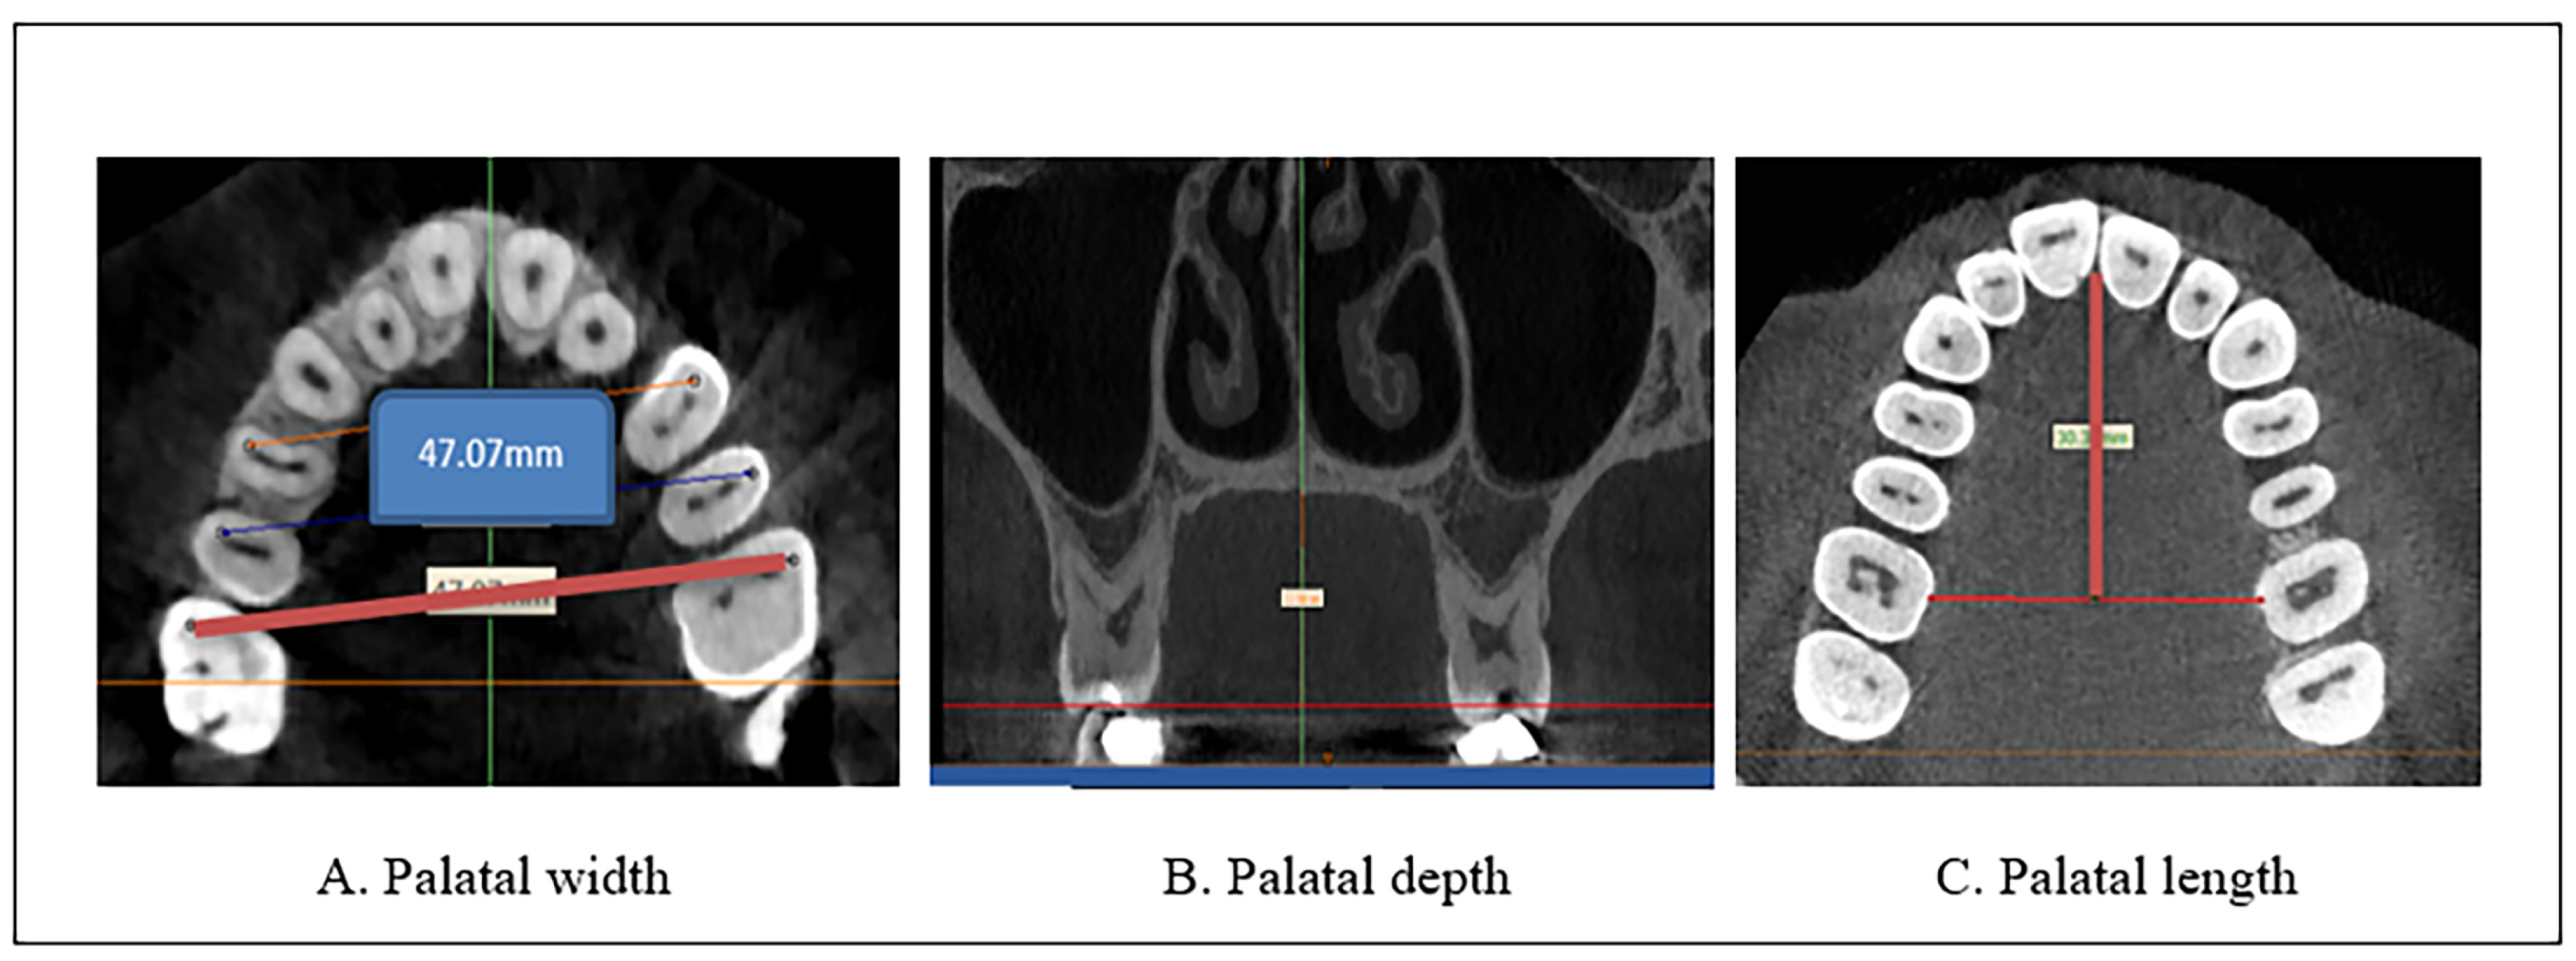

As illustrated in Figure 1A–C

Figure 1.

Palatal measurements with CBCT images using MIMICS software. (A) Palatal width (B) Palatal depth (C) Palatal length.

- Palatal width was measured by drawing lines from the mesiobuccal cusp tip of the maxillary first molar from one side to the other [19]. The exact location of the buccal cusp tips of the upper first molar was identified and checked in all the planes from the coronal plane [20] and even from the reference plane. Then, the palatal width was measured from the axial view. Using the axial plane for the evaluation allowed the accurate designation of the selected landmark without superimposing different landmarks [20]. The coronal and axial levels at which the position of the mesiobuccal cusp of the upper molar was identified differ from one case to another due to anatomical variations, but in most of the cases, they are between (66–73 and 45–50) slices, respectively.The measurements were performed on an axial view of the radiographs derived from the CBCT images (Figure 1A).

- Palatal depth is evaluated by the depth or height of the palate in the first molar areas [21]. The measurements were performed on a coronal slice of the radiographs derived from the CBCT images (Figure 1B).

- The palatal length was determined by measuring the linear distance from the mesial contact point of the upper central incisors to the midpoint of the linear distance between the two upper first molars, obtained from the axial view of the radiographs derived from the CBCT images (Figure 1C).